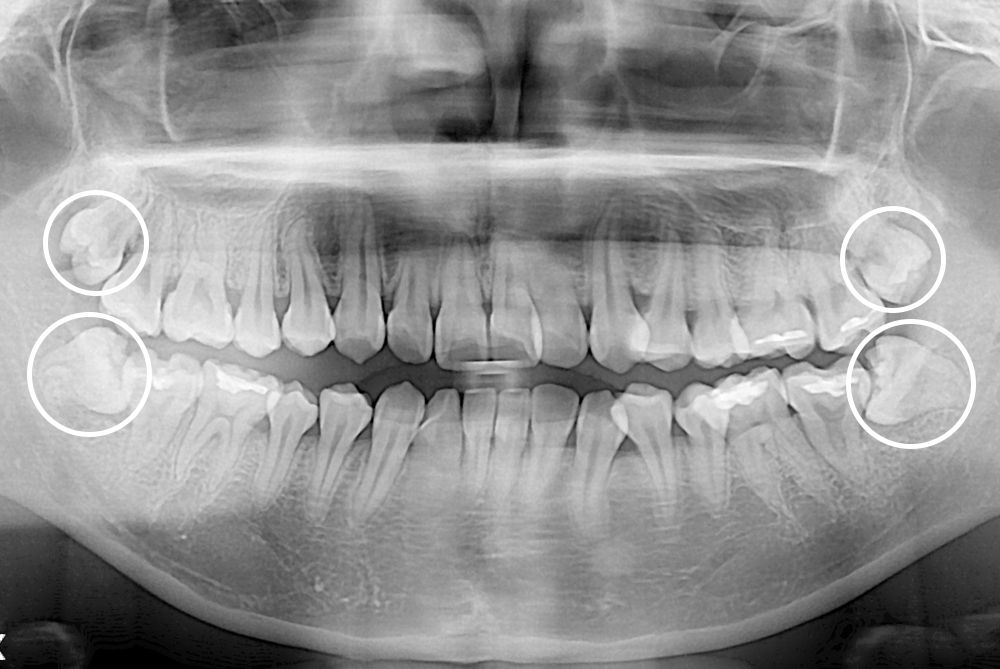

[사랑니] 매복 사랑니 발치

치료전 : 2019-05-15

세종치과는 구강악안면외과학 박사이신 원장님이 발치하는 치과입니다.